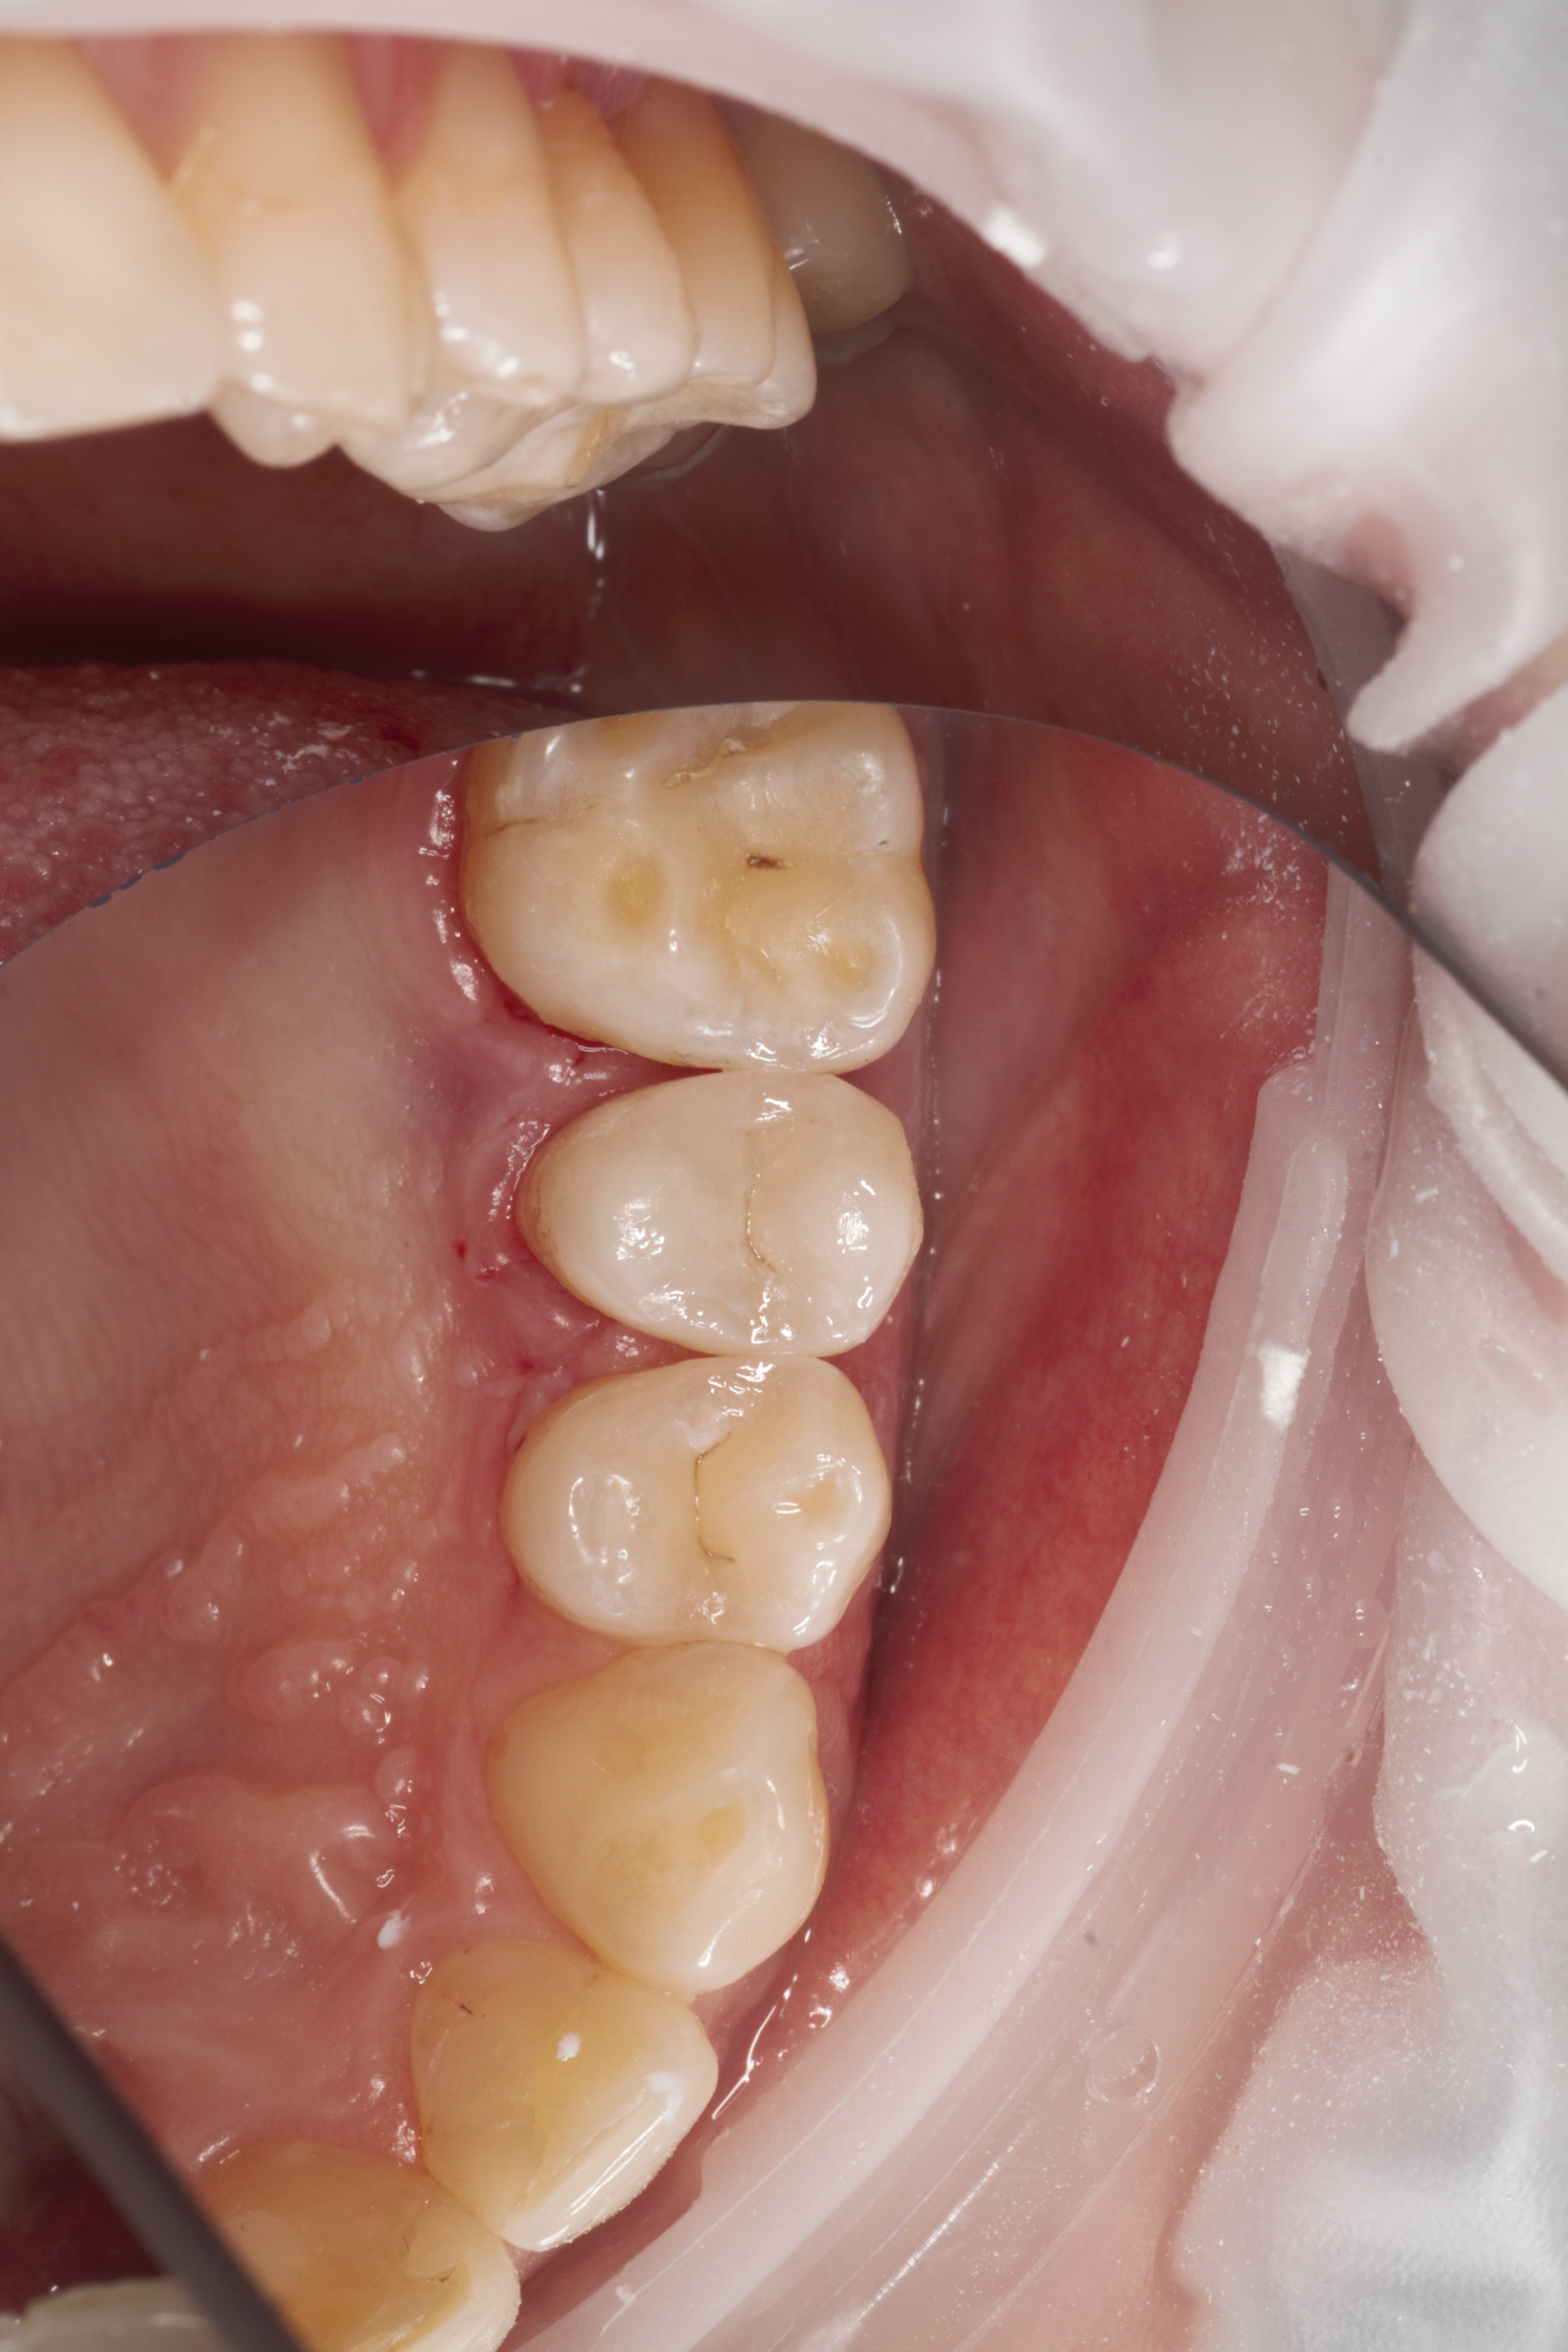

- Эстетическая реставрации жевательной и фронтальной группы зубов современными пломбировочными материалами, диагностика кариеса на ранних этапах развития, предупреждение образования вторичного кариеса в области запломбированных зубов

- Владение современными методиками пломбирования корневых каналов, обработки и распломбировки многокорневых зубов любой степени сложности